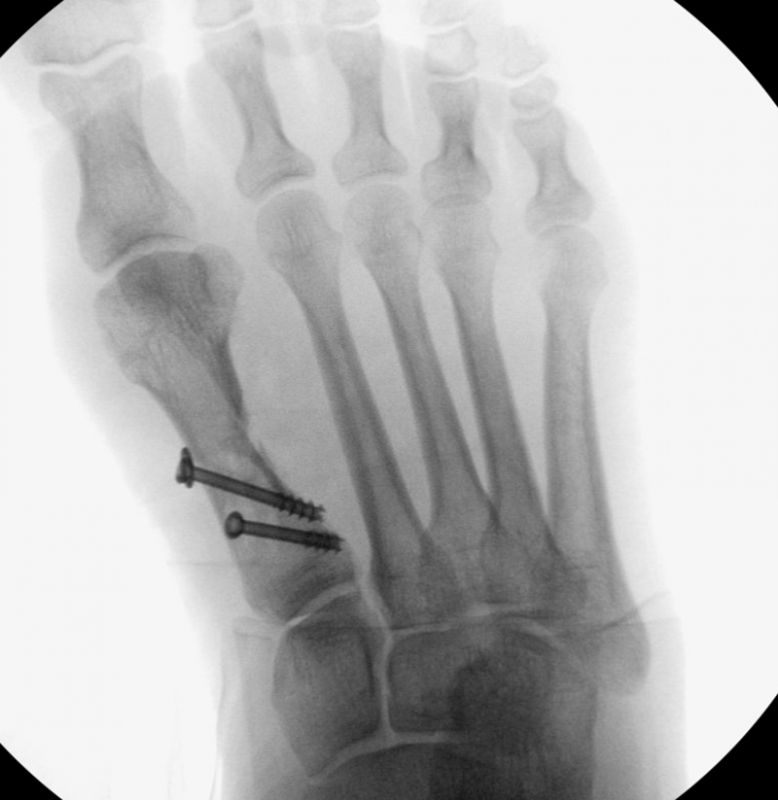

• Kanülierte Schrauben bis 50 mm Länge, 4 mm Durchmesser, Beilagscheiben.

• Gute Stabilität durch Stabilisierung mit einer oder zwei perkutanen Schrauben möglich.

• Röntgenkontrollen (Vorfuß d.p. und seitlich) postoperativ ohne Belastung. Weitere Kontrollen erfolgen 6 Wochen, sowie 3, 6 und 12 Monate jeweils unter Belastung.

• Bruch der medialen Kortikalisbrücke mit Verkürzung und Elevation des 1. Strahles. In diesem Fall muß die Länge des 1.Strahles durch eine quer zur Schaftachse plazierten Schraube gesichert werden. Als Alternative bietet sich eine lange Schraube durch den Schaft als intramedullärer Kraftträger an